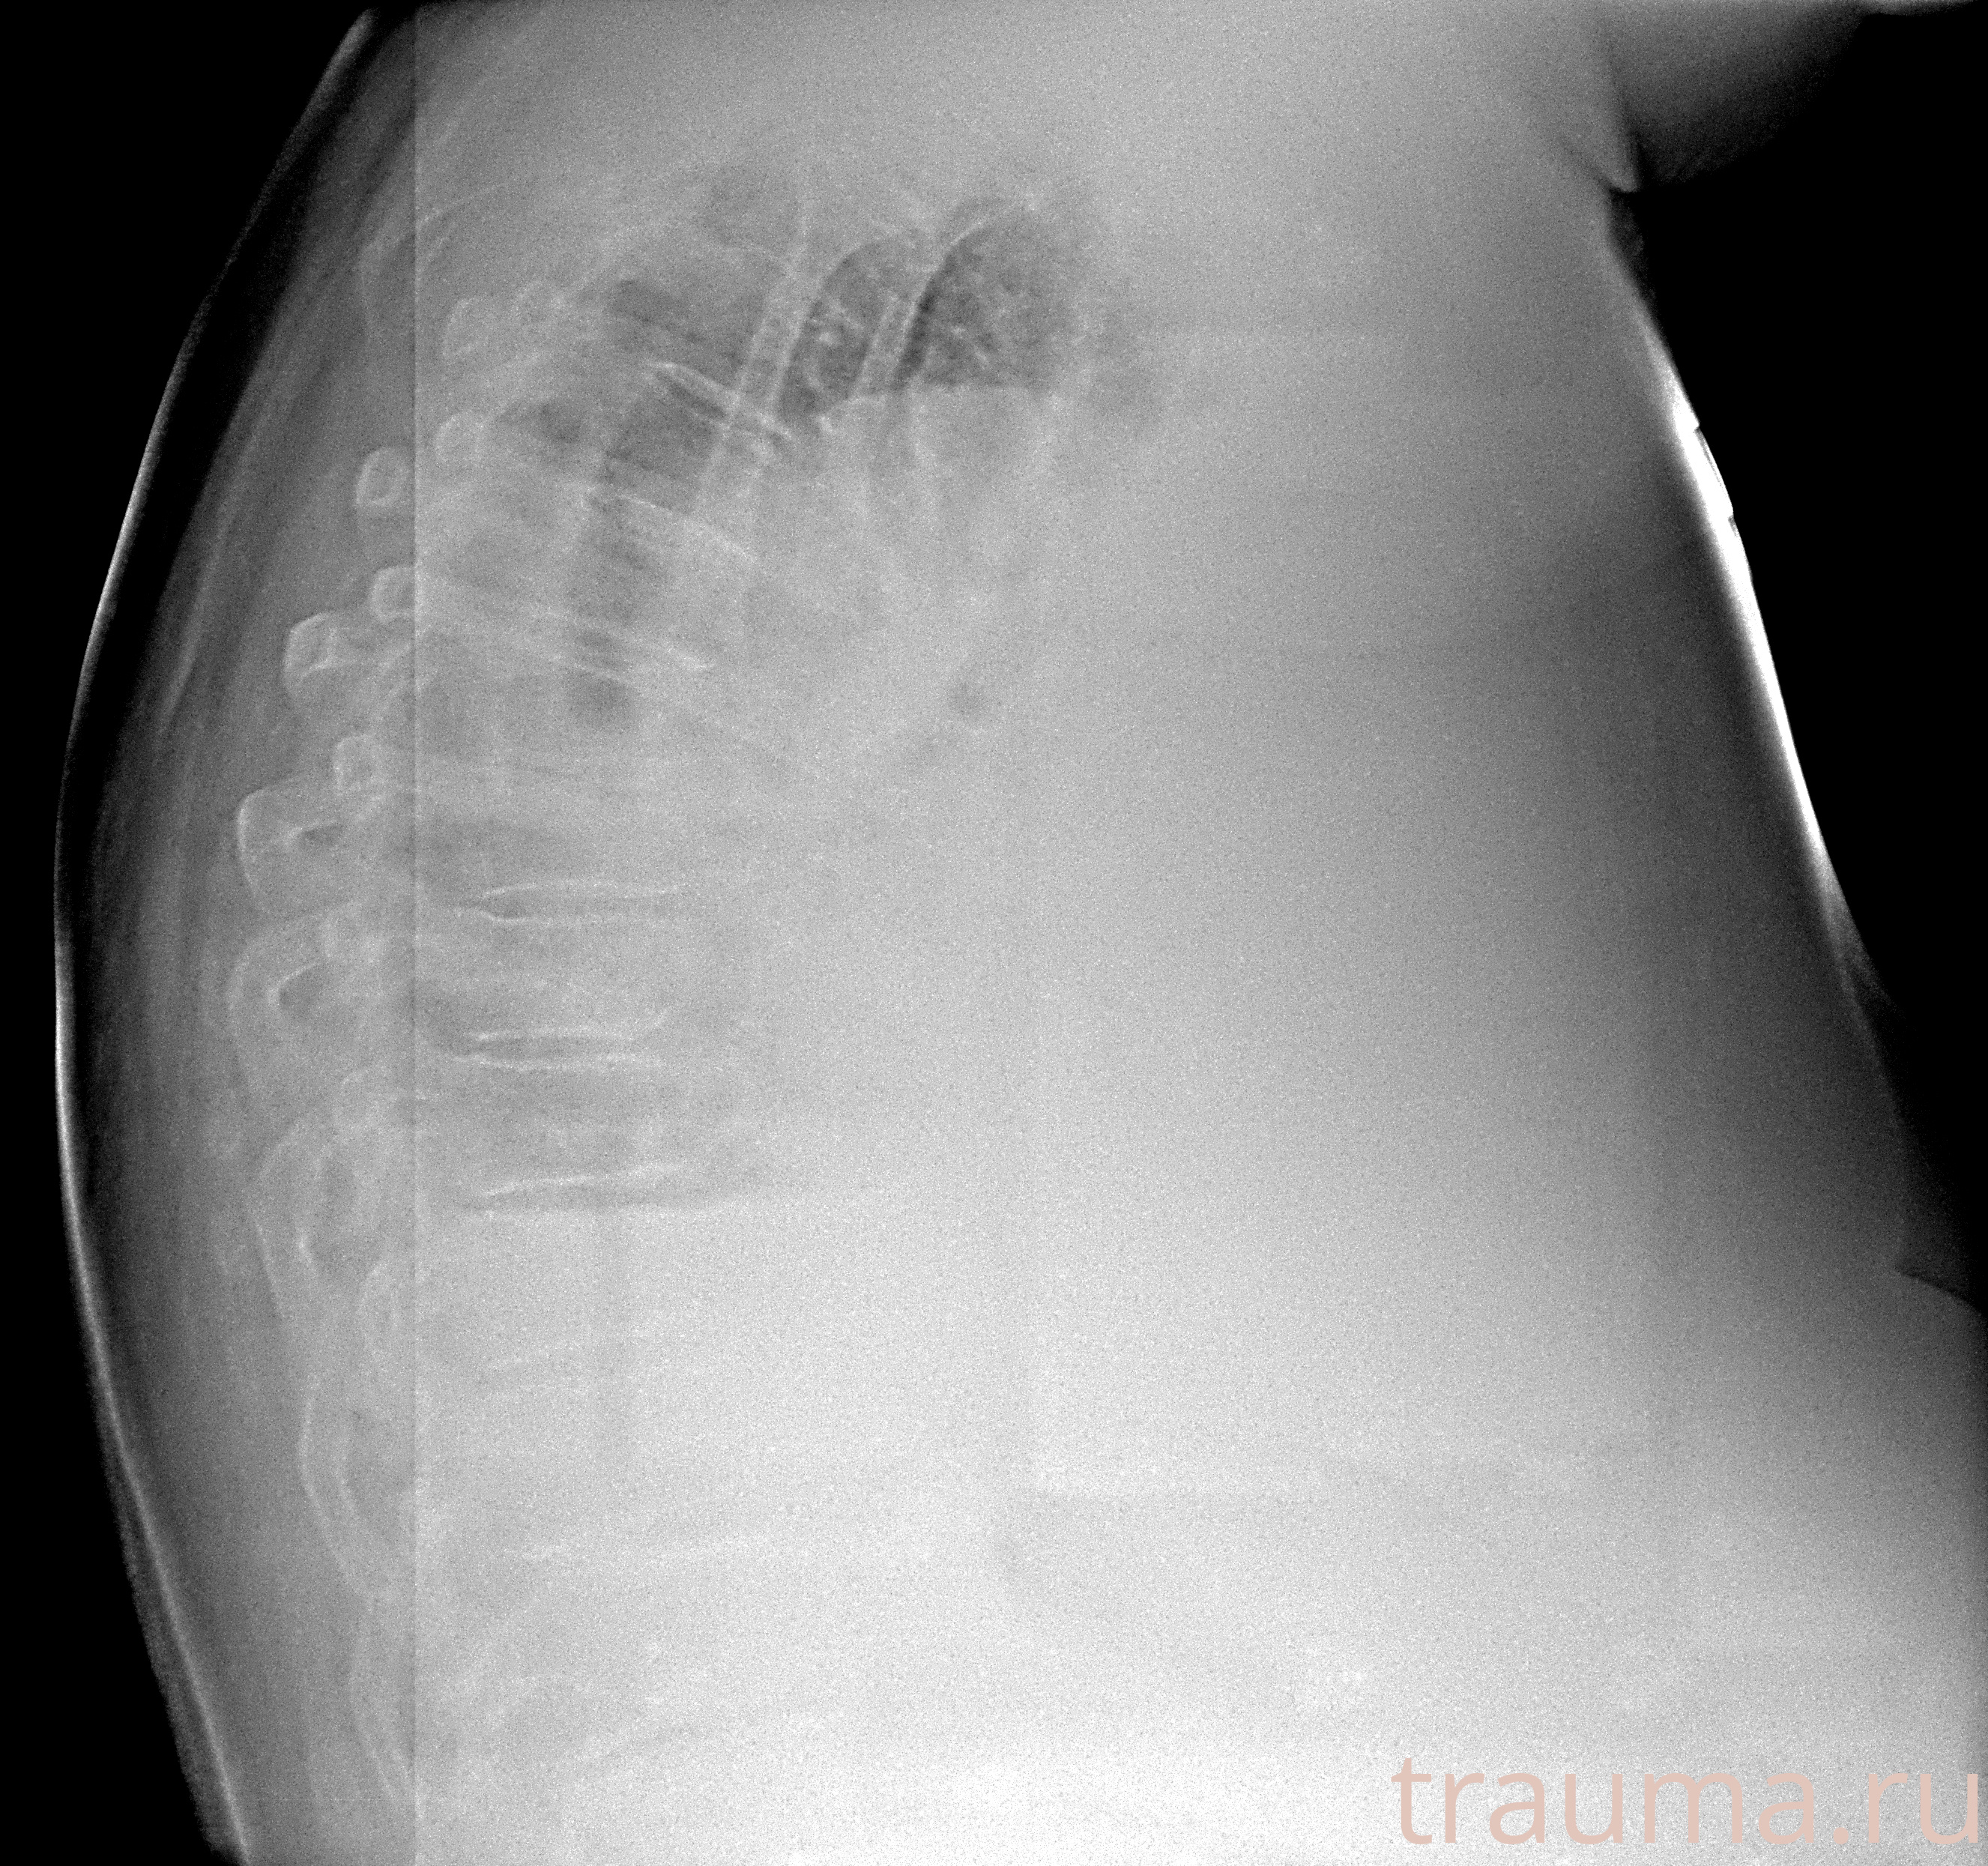

Рентген на дому: по вашему адресу приезжает врач-рентгенолог, травматолог-ортопед с мобильным рентгеновским аппаратом, проводит диагностику травмы или заболевания, делает необходимые рентгенограммы, дает рекомендации по дальнейшему лечению. Получить качественные снимки в домашних условиях возможно благодаря уникальной методике, разработанной МосРентген Центром для института  Склифосовского